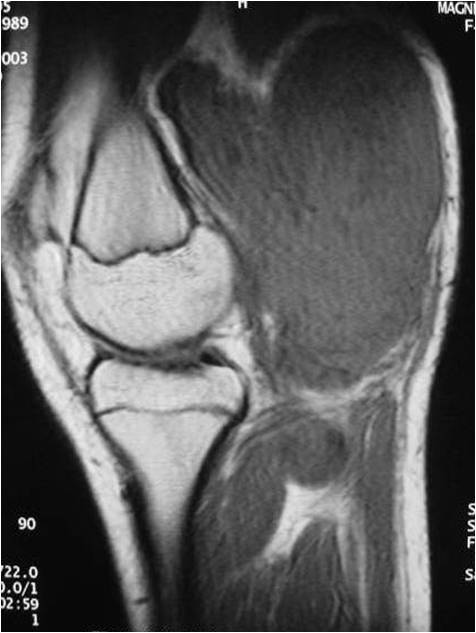

- Aggressive motheaten to permeative lesion

- Indistinct border in most cases

- Osseous destruction with a soft tissue component

- Chondroid matrix calcification may be present (60-70% of cases)

- Soft tissue mass

- Locally aggressive

- Cortical destruction in approximately half of cases

- Extension of tumor into adjacent soft tissues